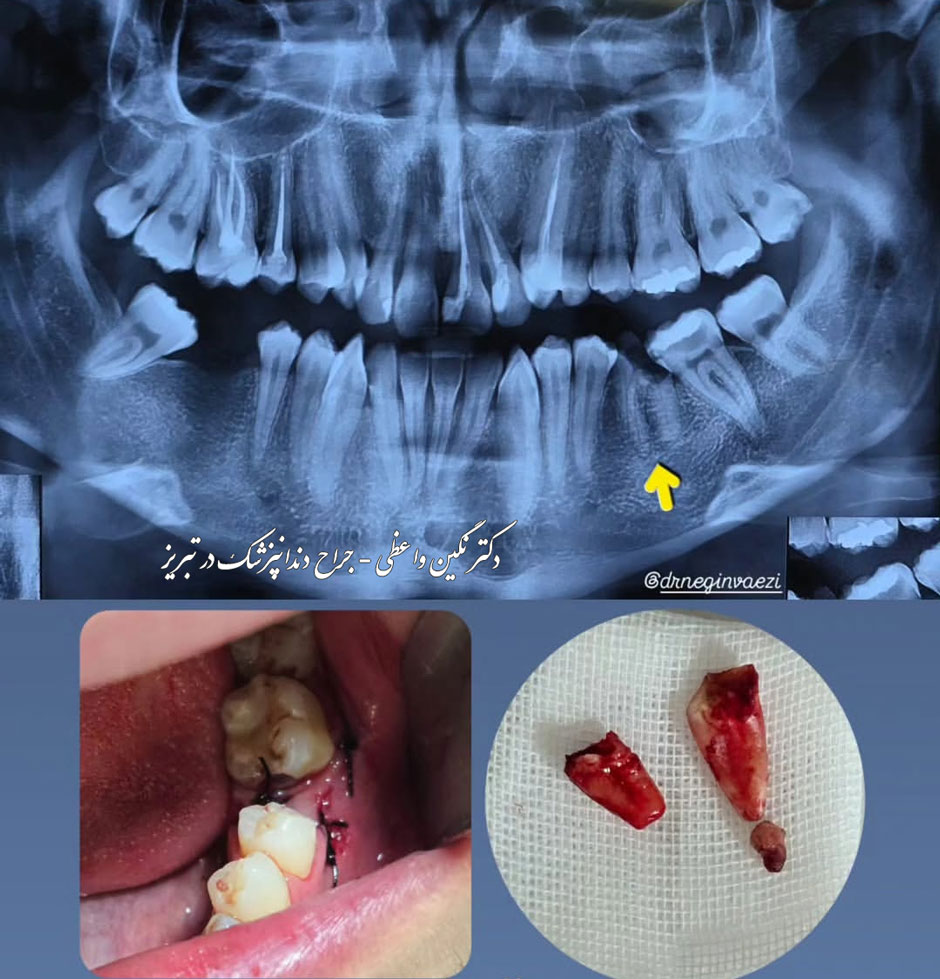

عکس جراحی دندان پوسیده و شکسته

چرا در برخی نمونه ها دندان کشیده شده چند تیکه است؟

دلایل مختلفی وجود دارد که یکی از مهمترین آنها پوسیدگی یا تخریب شدید دندان هست که هنگام خارج سازی تیکه تیکه می شود، گاهی وقت ها نیز، خود دندانپزشک جهت سهولت در خارج شدن و جلوگیری از خرد شدن دندان، آن را چند تیکه می کند تا خارج سازی آن راحتتر انجام شود.

عکس جراحی دندان شکسته

عکس دندان با تخریب شدید

عکس دندان شدیدا عفونی (عفونت کرده)

عکس خارج کردن ریشه های دندانی

آیا برای جراحی دندان نیاز به عکس رادیوگرافی می باشد؟

بله! دندانپزشک قبل از هرگونه جراحی اعم از دندان عقل یا ریشه دندان، عکس رادیوگرافی تجویز خواهد کرد و پس از آن اقدام به کشیدن و یا جراحی خواهد نمود.